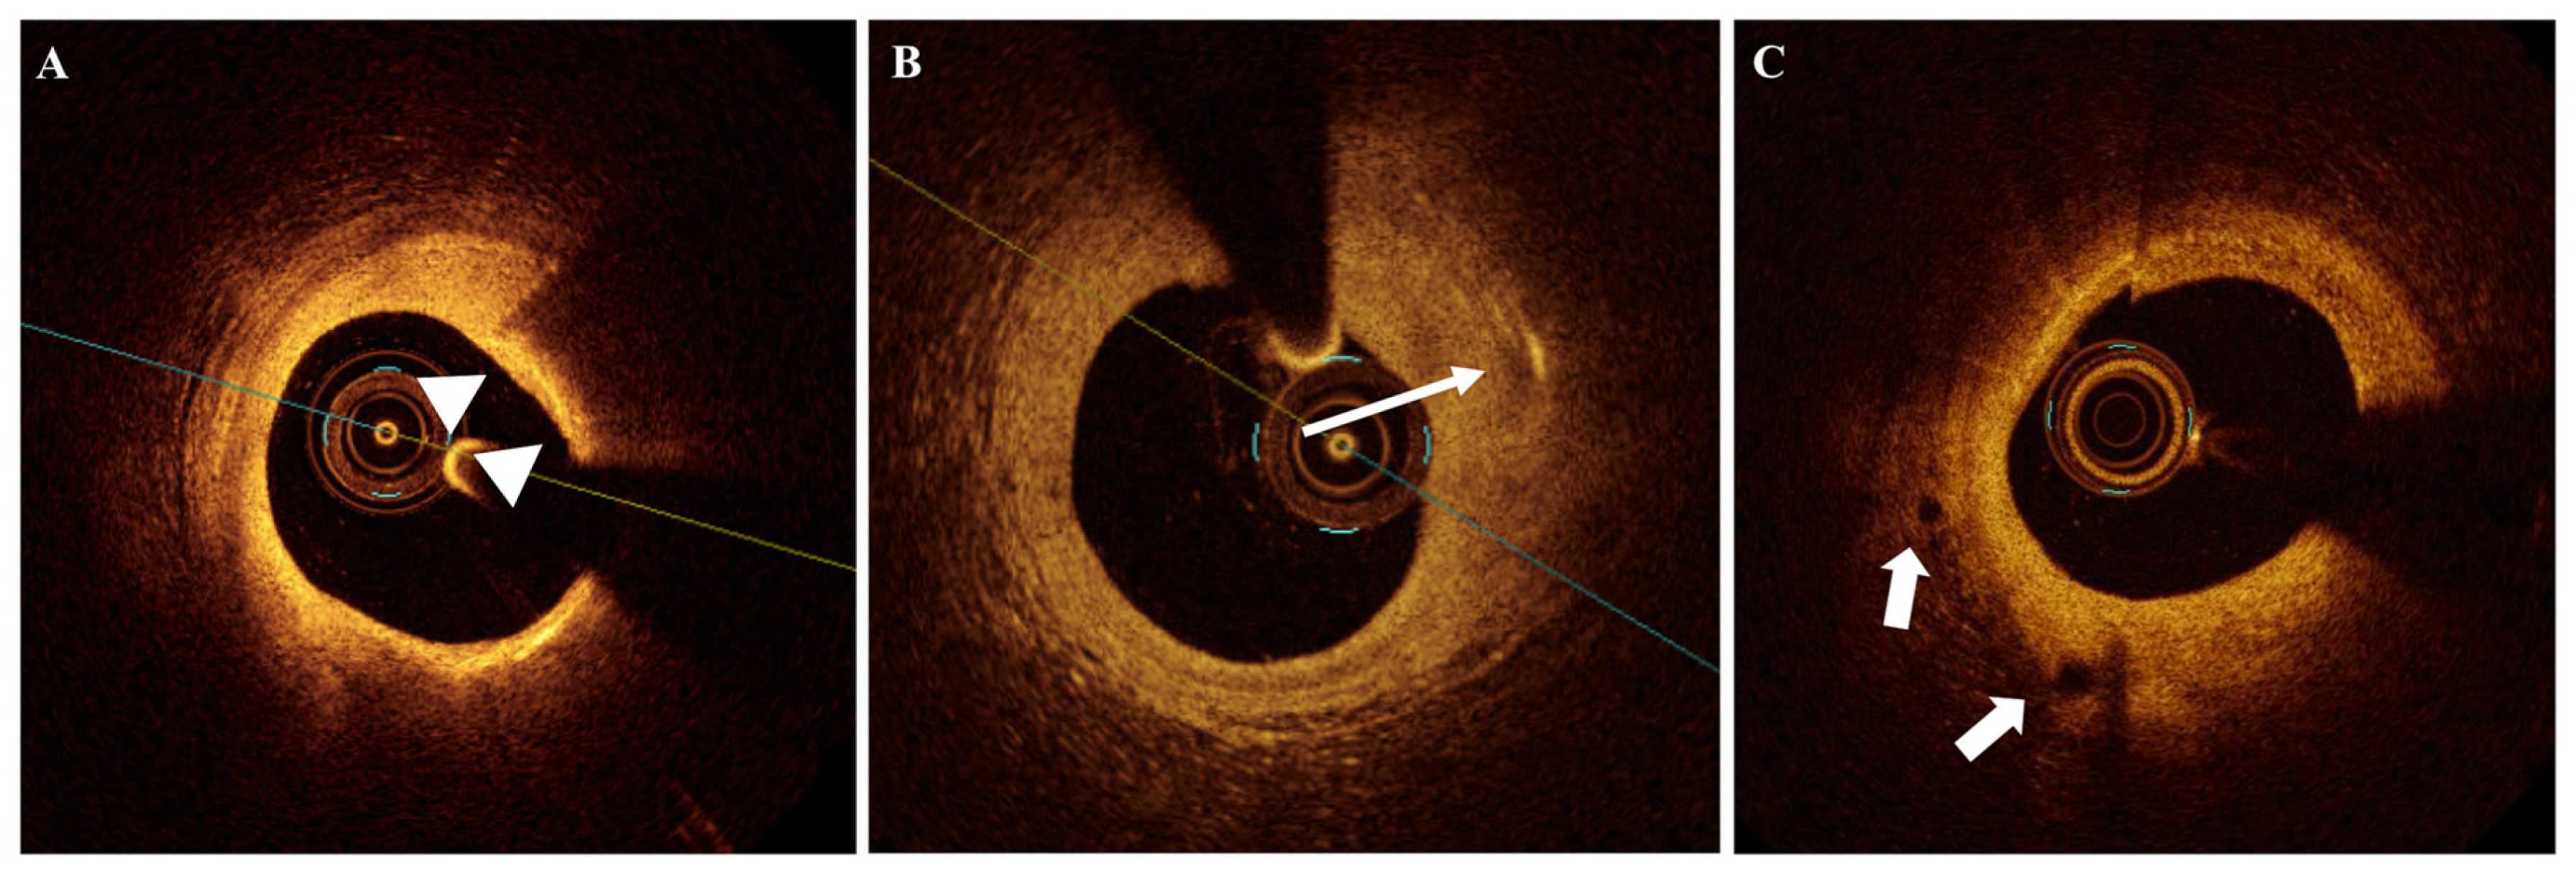

2.7. Calcifications

2.8. Previous Ruptures (Cavities Within the Plaque in Stable Patients)

1. Introduction